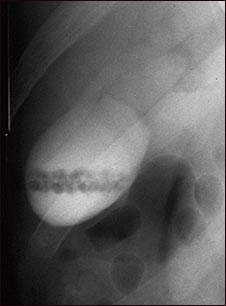

Colangiograma de cálculos

Colecistograma de un paciente con cálculos biliares.